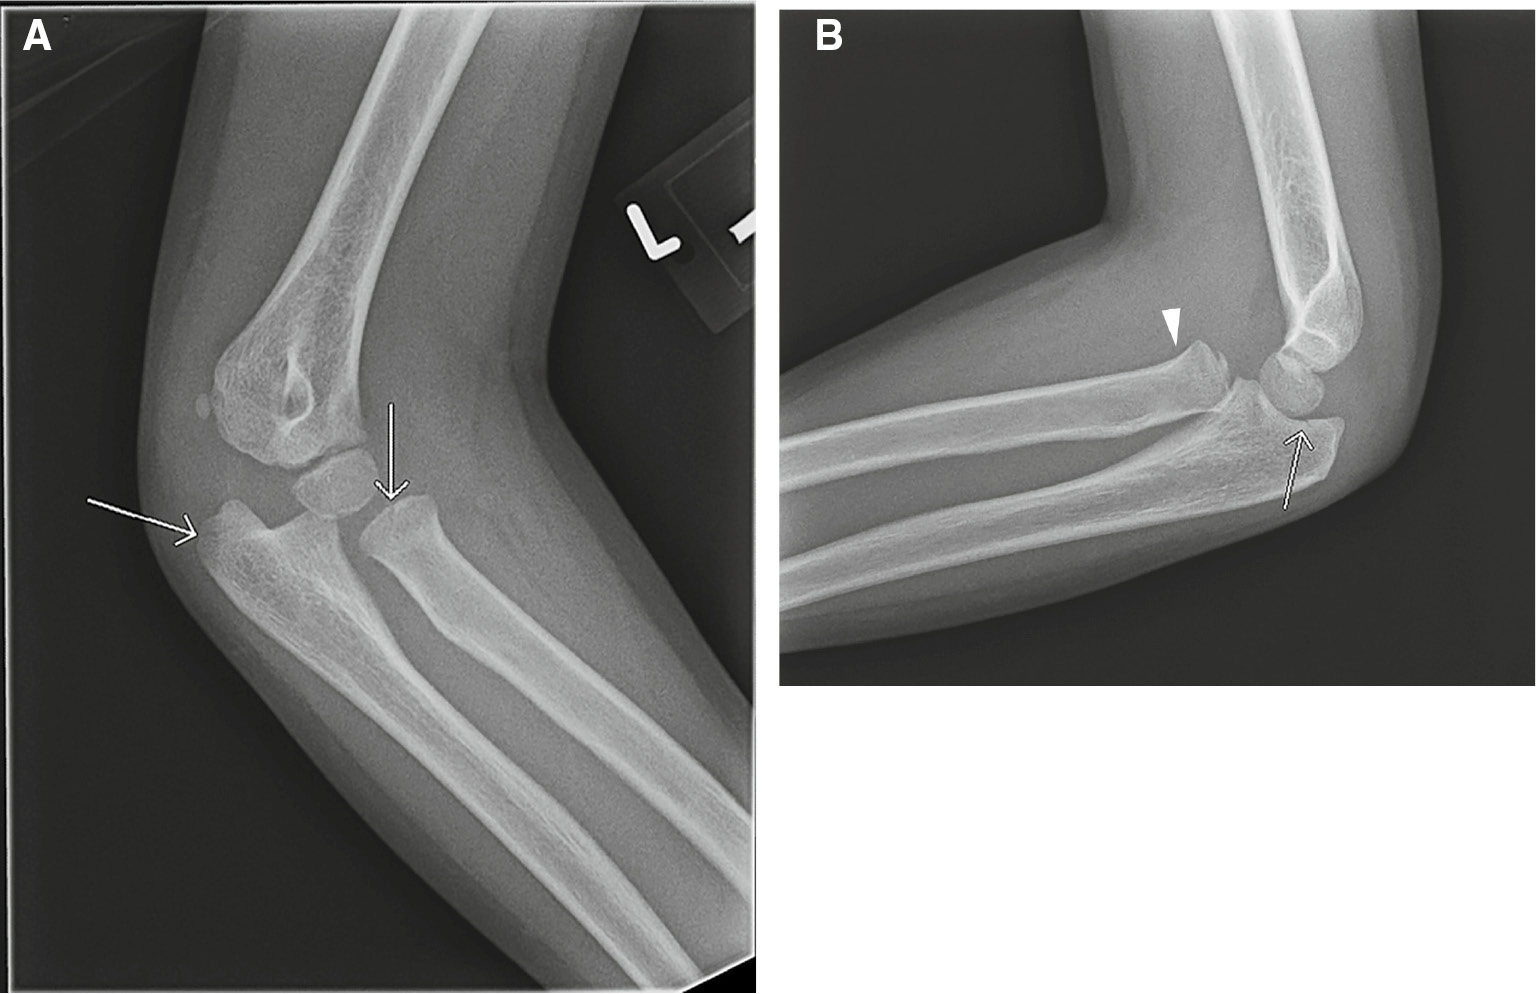

There are several inter-related factors that contribute to an incomplete evaluation of relevant image content in clinical practice, resulting in a missed or delayed diagnosis. Broadly, they are related to the radiologist’s search patterns, the radiologist’s pre-existing expectations, and human factors such as increasing clinical workload, fatigue, interruptions and distractions [3], [9], [12]. The most well-known is the phenomenon of satisfaction of search (SOS). It describes a situation during which the detection of an abnormality satisfies the search for meaning and results in premature termination of further search [13], [14]. In a seminal study in 1990, Berbaum et al. [15] showed that the addition of simulated pulmonary nodules in chest radiographs led to a significant reduction in the detection of native pulmonary nodules. SOS effects also lead to lower detection rates when multiple findings are present in clinical cases. Ashman et al. [16] showed that the detection rate for the first finding in bone radiography cases that contained multiple findings was about 78%, but detection of second and third findings decreased to approximately 40% (Figure 1). Subsequent experimental studies have shown that SOS effects appear to be the result of either a lack of visual inspection of other areas of the image, or a failure to recognize abnormalities where the image has been inspected [14], [17].

Figure 1: Satisfaction of search error.A 7-year-old male with elbow pain and limited range of motion after fall. Two of the four X-rays obtained are shown. Subtle, nondisplaced fractures of the radial head and olecranon were identified on oblique (A) and lateral (B) radiographs (arrows). An anterior dislocation of the radial head (arrowhead) was missed.

A 7-year-old male with elbow pain and limited range of motion after fall. Two of the four X-rays obtained are shown. Subtle, nondisplaced fractures of the radial head and olecranon were identified on oblique (A) and lateral (B) radiographs (arrows). An anterior dislocation of the radial head (arrowhead) was missed.